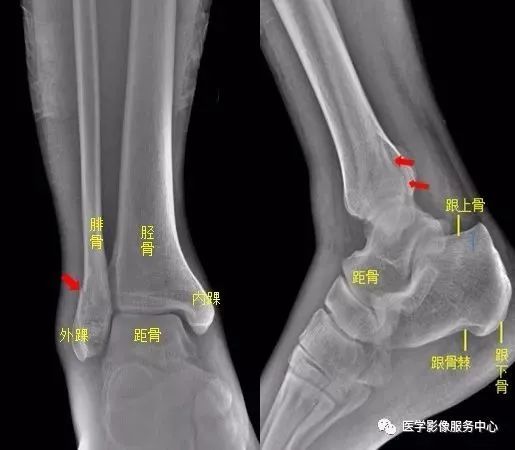

正常人右跟骨图片,右跟骨粉碎性骨折图片

11足部右足斜位示 右侧跟骨前部见骨折透亮线,右跟骨前部骨折.

正常人跟骨可见三角形的局限性透亮区,为生理性骨小梁稀疏区(箭头)